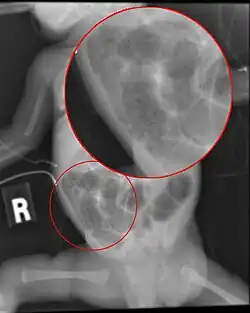

Diagnosis is usually suspected clinically, but often requires the aid of diagnostic imaging, most commonly radiography, which can show the intestines and may show areas with dead tissue or a bowel perforation.[18] Specific radiographic signs of NEC are associated with specific Bell's stages of the disease:[19]

- Specific radiologic signs (pneumatosis intestinalis or portal venous gas)

- Severe radiologic signs (pneumoperitoneum)

Ultrasonography has proven to be useful, as it may detect signs and complications of NEC before they are evident on radiographs, specifically in cases that involve a paucity of bowel gas, a gasless abdomen, or a sentinel loop.[21] Diagnosis is ultimately made in 5–10% of very-low-birth-weight infants (<1,500g).[22]